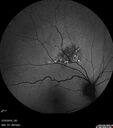

61 year old man with amelanotic choroidal nevus. Vision Normal - Stable over 4 years.

Amelanotic Choroidal Nevus - Multimodal Imaging577 views61 year old man with amelanotic choroidal nevus. Vision Normal - Stable over 4 years.00000